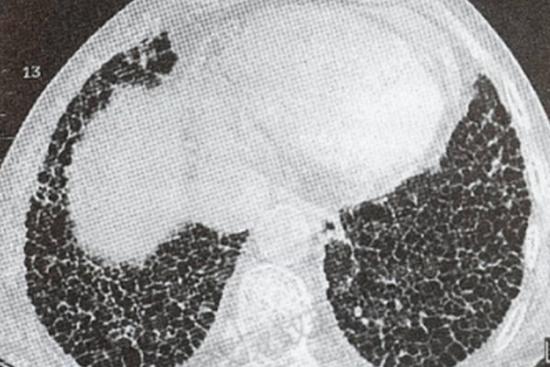

- 肺部少许纤维灶一般来说对身体的影响相对较小。这些纤维灶通常是比较稳定的,不会引起明显的症状。从影像学检查上看,纤维灶通常表现为局部的条索状、斑片状阴影。由于其范围较小,一般不会对肺部的正常功能造成严重的干扰。

- 虽然少许纤维灶本身可能并不严重,但如果纤维灶的数量逐渐增多或者范围扩大,就可能会对肺部功能产生一定的影响。在一些情况下,如果纤维灶是由于自身免疫性疾病引起的,那么随着疾病的进展,可能会导致肺间质纤维化等更为严重的肺部病变。一些患有类风湿性关节炎等自身免疫性疾病的患者,可能会出现肺部受累,表现为肺部纤维灶逐渐增多,进而影响肺部的气体交换功能,导致患者出现呼吸困难、咳嗽等症状。